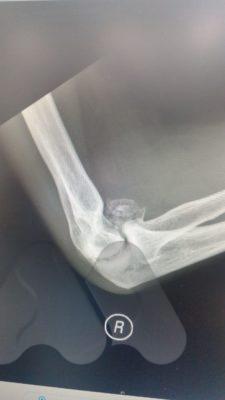

Elbow osteoarthritis is a degenerative joint disease where the smooth cartilage covering the bone ends, wear out, causing pain and stiffness. It can affect younger patients where a previous traumatic injury can lead to either ligamentous instability, severe scarring in the joint or cartilage injury and lead to progressive stiffness around the elbow which may or may not be accompanied by pain.

In cases where the main complaint is stiffness in the elbow, common activities like shaving, getting to the back of the head and face become difficult. X-Rays are a simple scan that can confirm extra bone formation in the joint which may be blocking movement. In these situations, a keyhole operation (arthroscopy) can be performed to remove loose fragments of bone, remove extra bone and release the tight capsule that surrounds the joint.

Pain in the elbow can relate to the inflammation of the joint lining (synovitis) that accompanies osteoarthritis or impingement related pain at the end ranges of movement where bone fragments can jam between the joint surfaces. If loose bodies are present in the joint, these can float around freely and intermittently cause jamming of the moving parts like a loose stone in a motor. Depending on the cause of pain, the treatment can be directed at reducing the inflammation with oral anti-inflammatories or corticosteroid injections to the joint. Surgical treatments include arthroscopic or open debridement of the joint to remove extra or loose fragments of bone that are impinging. If there is extensive joint involvement and these simple measures fail to relieve pain then a Total Elbow Replacement can provide good pain relief whilst maintaining movement.